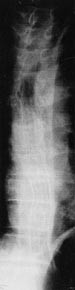

Fire måneder etter diagnosetidspunktet fikk pasienten brått økt dysfagi: Han hadde problemer med å svelge tabletter og var plaget med sliming. Tumor var nå 23 cm lang, bedømt ut fra CT-bilder og endoskopi. Oesophagus ble blokket til 15 mm. To stenter av udekket type (Ultraflex, Microvasive, Boston Scientific Corporation), hver på 10 cm, ble lagt distalt i oesophagus med 2 cm overlapping (fig 1). Pasienten hadde etter dette mindre dysfagi, men det gjenstod 5 cm av stenosen proksimalt i oesophagus som ikke var dekket av stent. En uke senere ble derfor en tredje stent av samme type satt inn. Proksimale begrensning av denne stenten ble liggende ca. 2 cm distalt for øvre oesophagusmunn (fig 2). Nå hadde pasienten ingen dysfagi. Han hadde ingen fremmedlegemefølelse eller smerte av stentene og heller ingen dyspné, men fortsatt noe sliming.